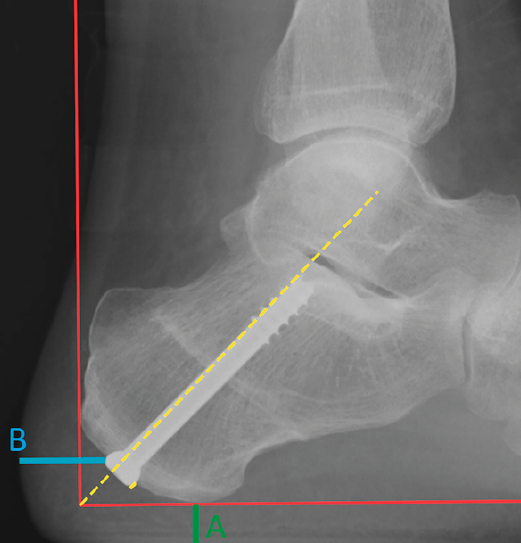

Se realizó una radiografía lateral en carga a todos los pacientes a los 3 meses de la cirugía y se midieron una serie de parámetros radiológicos. Para ello, utilizamos de referencia 2 líneas ortogonales entre sí que se encuentran en la tuberosidad posterior del calcáneo en una radiografía lateral en carga: una paralela al suelo que pasa por el punto más inferior de la tuberosidad del calcáneo o la cabeza del metatarsiano más descendido; y otra línea perpendicular a esta, tangente a la parte más posterior de la tuberosidad (Figura 3). Sobre estas líneas se midieron las siguientes variables que representan el almohadillado (distancia tornillo-piel) inferior (A), posterior (B) y el nivel de protrusión del material, si lo hubiera. Los niveles negativos se tomaron como 0.

Figura 3. Radiografía lateral en carga.